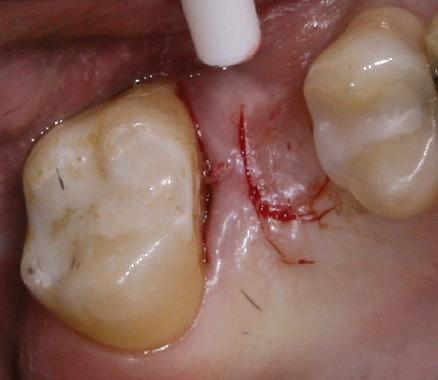

Reprepararea intraorală a bonturilor Acest pacient prezenta dentiţia maxilară compromisă, refuzând proteza mobilizabilă. Prin abordarea în etape, se menţin o parte din bonturile dentare naturale; s-a observat recesie în momentul amprentării pentru cel de-al doilea grup de implanturi.

Fig. 1 prezintă pacientul după inserarea primului set de bonturi implantare individualizate; dinţii naturali adiacenţi

sunt încă prezenţi pentru a susţine puntea provizorie.

Şapte luni mai târziu (fig. 2), acele bonturi individualizate din prima etapă au manifestat semne de recesie de 1-3mm. Atitudine: S-a decis reprepararea intraorală a tuturor bonturilor (fig. 3), astfel încât toate marginile bonturilor să fie la nivelul sau sub marginea gingivală (de notat că 1.1. şi 2.1. au fost submersaţi ulterior pentru a avea sprijin implantar deplin).

Deşi reprepararea a îmbunătăţit marcat estetica finală, a necesitat aplicarea şnurului de retracţie, amprente noi şi turnări noi.

Un caz separat dar similar ilustrează în figurile 4 și 5 reprepararea intraorală a bontului.

Cazul (1): Reprepararea intraorală a bonturilor Figurile

1. Aspect după inserarea primului set de bonturi implantare individualizate.

2. După 7 luni, bonturile individualizate din prima etapă au prezentat recesie de 1-3mm.

3. Bonturile repreparate intraoral.

Alt caz (1) Figurile

4. După osteointegrarea implantului 2.4., s-a observat recesia în etapa de amprentare a implantului 2.5.; s-a decis reprepararea marginilor bontului individualizat CAD/CAM 2.4. Înainte de preparare s-a aplicat şnur de retracţie pentru a evita lezarea ţesutului şi a îmbunătăţi vizibilitatea dintelui 2.3. şi a marginii bontului implantar individualizat. Aşa cum era de aşteptat, recesia a fost mai mare de-a lungul versantului distal al bontului 2.4. adiacent locului de extracţie vindecat/cu implantul mai nou.

5. Bontul individualizat aplicat (2.5.) cu bontul repreparat anterior (2.4.). Nu a survenit recesie nouă de o perioadă de peste 3 ani.